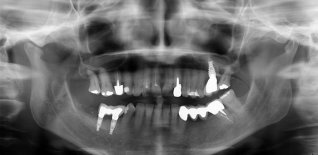

Mancanza dei denti postero inferiori di destra in assenza di osso sufficiente per poter posizionare degli impianti (spessore osso residuo meno di 2 mm).

Eseguito innesto d'osso in blocco e dopo circa 4 mesi inserzione degli impianti.

Successivamente sono stati applicati degli elementi dentari.